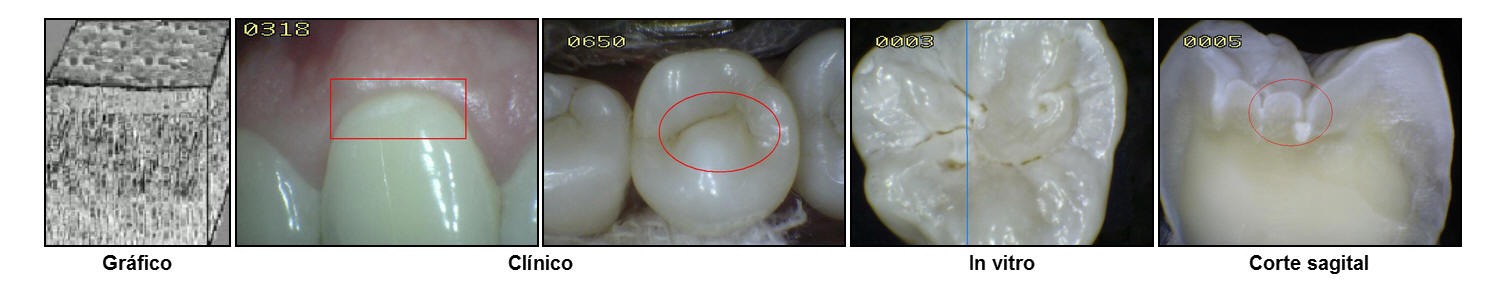

En la imagen

se muestra en color rojo las áreas de estancamiento de la placa

bacteriana en las superficies oclusales, espacios interproximales y los cuellos dentarios. Si la placa

no es

eliminada períodicamente las posibilidad de una lesión cariosa

es alta.

produce una pérdida de integridad superficial y/o cavidad en el esmalte. La fotografía muestra un premolar que fue extraído por motivos ortodóncicos-periodontales. Antes de la extracción el diente fue

cuidadosamente examinado para ver si estaba cariado.

El examen clínico usando espejo y sonda solo detecto

cálculos en el área gingival en las superficies interproximales; no existía

evidencia de deterioro al pasaje del hilo dental entre el

espacio interproximal y el punto de contacto.

Radiografías

de aleta mordible

(bite-wing) fueron tomadas a una exposición normal, y examinadas bajo lente de

aumento; no se encontró ninguna evidencia de caries. .

No

obstante, examinando el diente extraído después de seco y limpio, puede observarse sin dificultad una pequeña región

blanca sobre la superficie proximal (Ovalo en color rojo) Esta es la mancha blanca

que representa la más incipiente evidencia macroscópica de

caries; la superficie del esmalte que cubre esta lesión está

intacta y correctamente mineralizada, sin que pueda detectarse

diferencia al tacto con una sonda de exploración.

La razón por

la que esto es así, es que en la

lesión temprana de esmalte, la desmineralización ocurre

de manera predominante a nivel subsuperficial. La superficie

afectada por esta lesión incipiente aparece intacta y bien mineralizada.